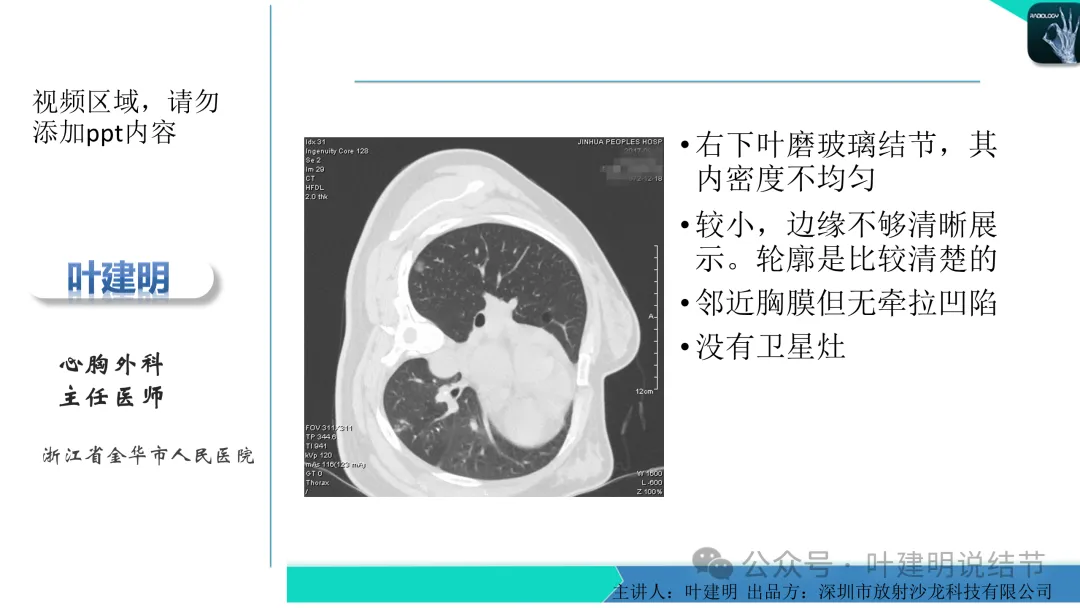

早在2020年时,我受邀在《放射沙龙》做过一个系列的精品课,当时专门总结分析过各类良恶性肺结节与肿块的影像特征,这是当时关于微浸润性腺癌影像特征的分析,今天看来仍基本不太需要改变,大家有兴趣的可以参考: